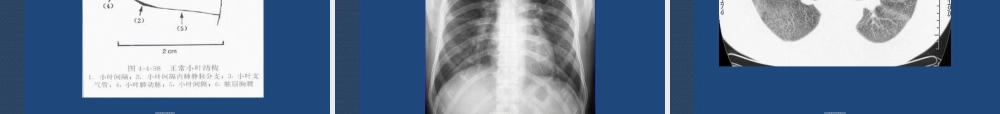

肺弥漫性结节和结节样致密(zhìmì)影的影像诊断第第第第第第第第第第弥漫性肺病(fèibìng)(diffuselungdisease,DLD)是指累及全部或几乎全部肺部,并在胸片或CT上形成各种表现的破坏性或限制性肺部疾病,是一种非特异性术语。第第第第第第第第第第弥漫性肺病的基本特征:1.分布:多灶性或弥漫2.形态:多样化或混杂3.部位:间质和实质浸润4.病理:多种类型和机制DLD约200-300种疾病,其中2/3病因(bìngyīn)不明第第第第第第第第第第影像表现(biǎoxiàn)(主要是)分型:网线状阴影结节状阴影高密度片影低密度囊片影肉芽肿阴影混合型阴影第第第第第第第第第第多发结节的表现:大小(dàxiǎo)形态密度背景来源和分布伴随征象第第第第第第第第第第大小分类(fēnlèi)≤粟粒结节≤微结节≤小结节≤中结节≤:大结节第第第第第第第第第第第第第第第第第第第第形态表现(biǎoxiàn):圆形或类圆形不规则形树芽状或分支状星状短棒状或弧形第第第第第第第第第第第第第第第第第第第第密度(mìdù)表现:实性囊性钙化性混合型第第第第第第第第第第第第第第第第第第第第第背景(bèijǐng)的分类:网状结节磨玻璃结节肺气肿结节正常背景下的结节第第第第第第第第第第第第第第第第第第第第第第分布与来源(láiyuán):1.间质性---淋巴道来源2.气腔性---吸入性3.气道性---气道壁4.随机性---血行性第第第第第第第第第第第第第第第第第第第第第第第第第第第第第第第第第肺的组成结构(jiégòu):气道系统支气管到细支气管并延续到肺泡。血管系统由肺动脉到细小肺动脉到肺泡的毛细血管,肺静脉到细小的肺静脉。间质结构由支气管动静脉、淋巴管组成。以上三者组成复杂的肺结构。第第第第第第第第第第第弥漫性肺疾病表现的解剖基础肺的间质:即肺的框架结构,包括中央间质支气管和血管(xuèguǎn)周围间隙,自肺门向外周放射。周围间质小叶间隔、胸膜下间隙。第三间质肺泡壁间隙。第第第第第第第第第第第小叶结构:每一个细支气管连同它的各级分支以及分支末端(mòduān)的肺泡构成一个肺小叶,或称次级肺小叶。小叶间隔:构成小叶的边缘。小叶核心:小叶动脉和细支气管。小叶实质:小叶核心的外围结构,呼吸性细支气管...